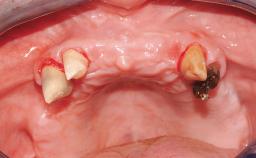

Conventional Loading of Six Implants in the Mandible and Final Restoration with a Full-Arch Metal-Ceramic FDP

A 68-year-old, completely edentulous male patient presented for evaluation and treatment options. He reported excellent general health and was taking no regular medication. He had been edentulous for approximately 12 years, having lost his teeth to periodontal disease and dental caries. The patient’s chief complaint was incompetent function. His secondary concerns included his appearance and the desire for a predictable outcome. He attributed his reduced functional capacity to his lower complete denture, which he described as poor. He was particularly concerned with the denture’s instability and poor fit. In general terms, he was satisfied with the maxillary complete prosthesis. The maxillary prosthesis was characterized by adequate retention, stability, and support, although the fit was considered less than ideal.

Case Type Edentulous Mandible

Jaw Mandible

Area Full-Arch

# of Teeth All